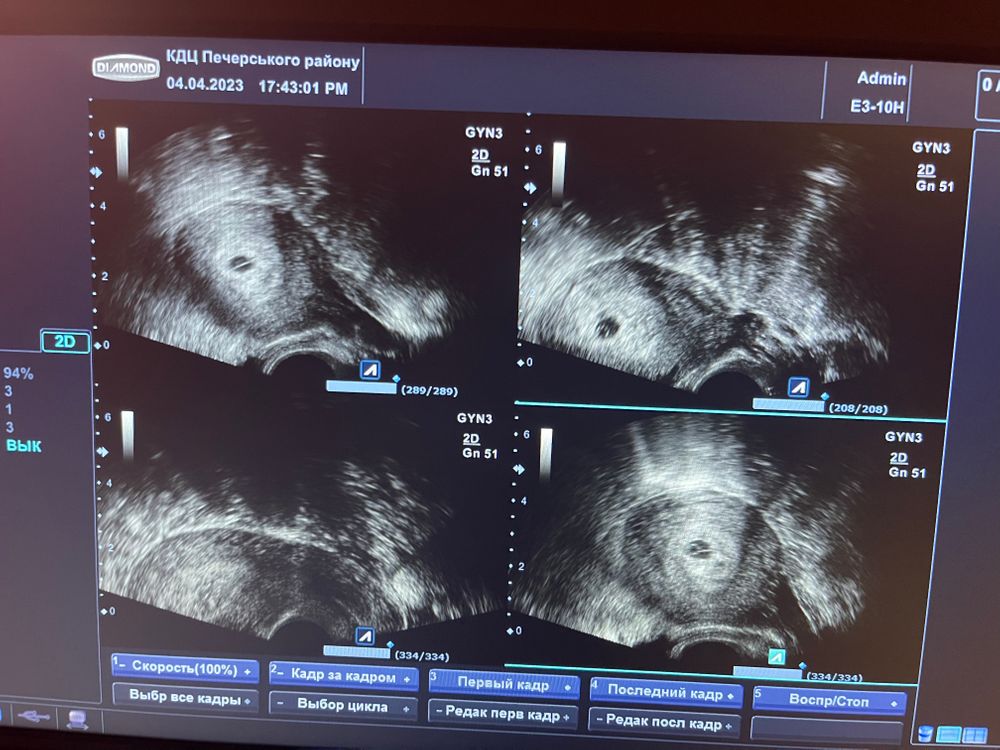

УЗИ после мазни

После мазни пошла на следующий день к гинекологу на узи, поставили 5 недель, маточная беременность, небольшая отслойка сказали, к

мазня прекратилась, сижу на утрожестане.

елинстевнное что смущает врача это перегородке в пробном яйце, но сказала паниковать рано, может быть как плохому так и хороший исход в виде многоплодный беременности